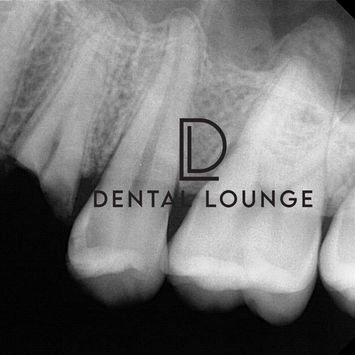

Pre-operative X-ray showed:

Fractured tooth with retained buccal and palatal roots

Long roots embedded in very dense bone